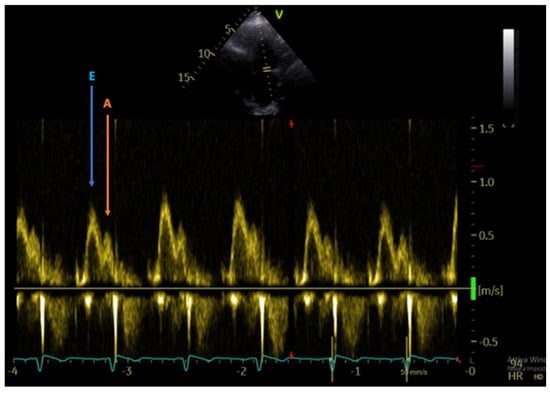

2.5. Evaluation of Diastolic Function

- StGoar, F.G.; Gibbons, R.; Schnittger, I.; Valantine, H.A.; Popp, R.L. Left ventricular diastolic function. Doppler echocardiographic changes soon after cardiac transplantation. Circulation 1990, 82, 872–878. [Google Scholar] [CrossRef]

- Valantine, H.A.; Appleton, C.P.; Hatle, L.K.; Hunt, S.A.; Billingham, M.E.; Shumway, N.E.; Stinson, E.B.; Popp, R.L. A hemodynamic and Doppler echocardiographic study of ventricular function in long-term cardiac allograft recipients. Etiology and prognosis of restrictive-constrictive physiology. Circulation 1989, 79, 66–75. [Google Scholar] [CrossRef] [PubMed]